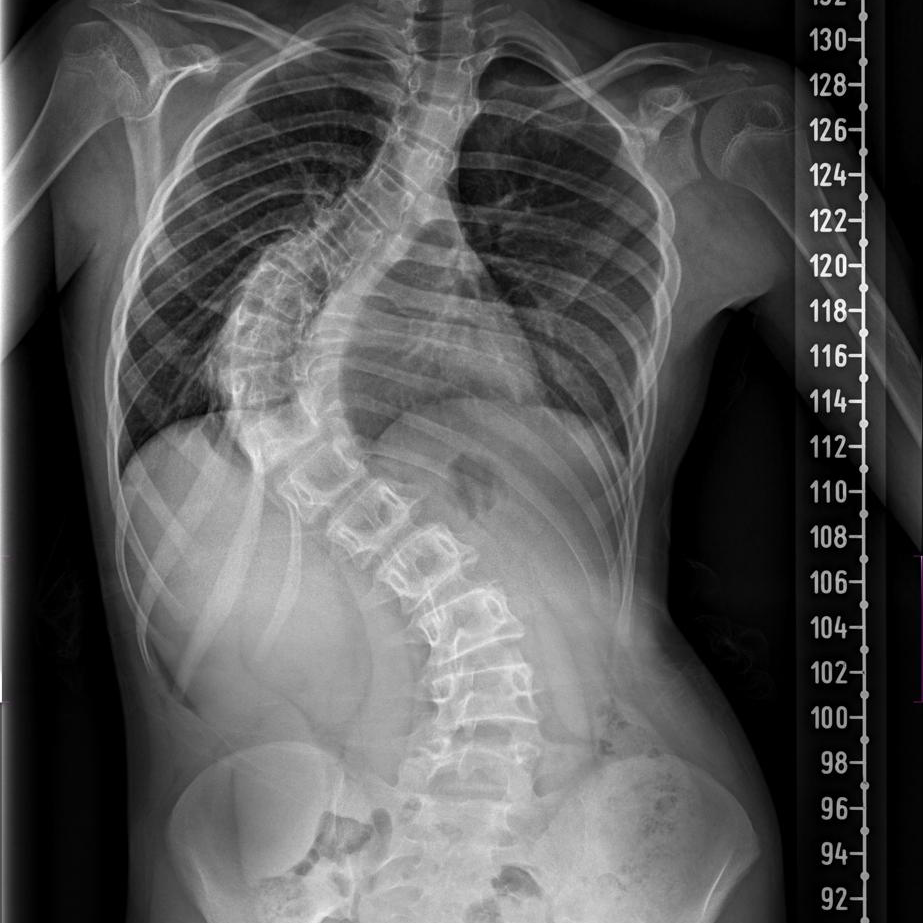

La escoliosis es una desviación lateral de la columna vertebral que suele acompañarse de rotación de las vértebras. Se diagnostica cuando la curva medida en una radiografía (ángulo de Cobb) supera los 10 grados. Puede aparecer en cualquier etapa de la vida y siempre requiere una valoración especializada para definir el mejor abordaje.

- Radiografía: determina ángulo y localización de la curva.